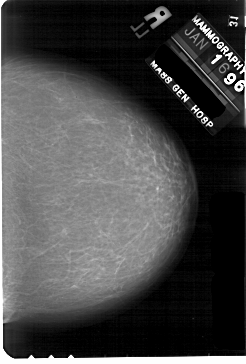

A_1869_1.LEFT_CC

RIGHT_CC LINES 5446 PIXELS_PER_LINE 3676 BITS_PER_PIXEL 12 RESOLUTION 43.5 NON_OVERLAY